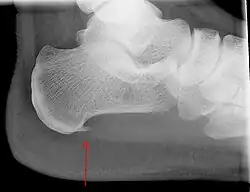

An incidental finding associated with this condition is a heel spur, a small bony calcification on the calcaneus (heel bone), which can be found in up to 50% of those with plantar fasciitis.[6] In such cases, it is the underlying plantar fasciitis that produces the heel pain, and not the spur itself.[13] The condition is responsible for the creation of the spur, though the clinical significance of heel spurs in plantar fasciitis remains unclear.[12]

Medical imaging is not routinely needed. It is expensive and does not typically change how plantar fasciitis is managed.[15] When the diagnosis is not clinically apparent, lateral view X-rays of the ankle are the recommended imaging modality to assess for other causes of heel pain, such as stress fractures or bone spur development.[7]

The plantar fascia has three fascicles-the central fascicle being the thickest at 4 mm, the lateral fascicle at 2 mm, and the medial less than a millimeter thick.[19] In theory, plantar fasciitis becomes more likely as the plantar fascia's thickness at the calcaneal insertion increases. A thickness of more than 4.5 mm ultrasound and 4 mm on MRI are useful for diagnosis.[20] Other imaging findings, such as thickening of the plantar aponeurosis, are nonspecific and have limited usefulness in diagnosing plantar fasciitis.[13]